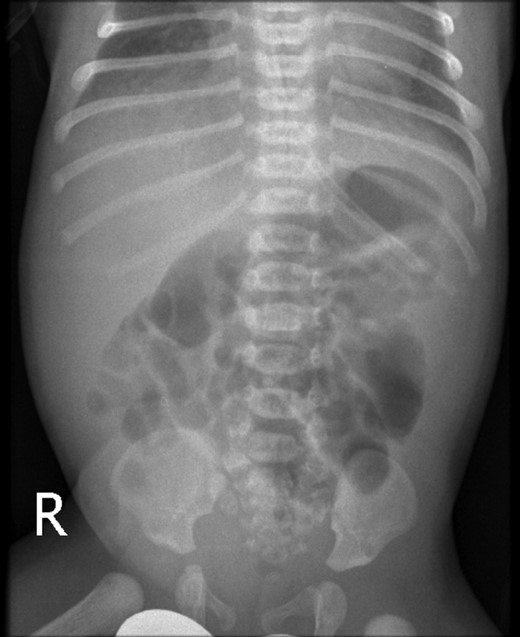

A 2-day-old girl was referred to our service with sudden onset of severe hematemesis. Prenatal history was significant for intrauterine growth retardation. She was born at the gestational age of 37/40 with a birth weight of 2.1 kg. On examination she was found to have dysmorphic features suggestive of Down's syndrome, along with hypotonia, intercostal muscle retraction and a mildly distended epigastric region. She was suspected of meconium aspiration and sepsis. Her initial investigations revealed WBC of 20 100 μl, Hb of 16.8 g/dl, platelets of 114 000/μl and CRP of 10 md/l. After intravenous antibiotics, she remained stable but on Day 2 of life, she was noted to have high levels of orogastric aspirates mixed with blood. A plain X-ray revealed a dilated stomach and duodenum, with air in the distal small bowel (Fig. 1). An APT test was negative. Repeat laboratory evaluation revealed WBC of 23 200 μl, Hb of 10.1 g/dl and platelets of 140 000/μl. She was started on ranitidine 10 mg daily but she continued to have fresh blood in her orogastric tube and her hemoglobin level dropped to 8.0 g/dl with INR 10, PT 120′ and APTT 180′. She was managed accordingly and after resuscitation, an upper GI contrast study was performed to rule out malrotation or mid-gut volvulus. Her upper GI contrast suggested an incomplete duodenal obstruction (Fig. 2). To look for a source of bleeding, an upper GI endoscopy was not performed due to duodenal obstruction and a risk of perforation. The baby was taken to the operating theater for exploration to determine the cause of her ongoing hematemesis and to correct her duodenal obstruction. On exploration, her stomach and proximal duodenum were dilated with a narrowing noted in the second part of the duodenum. There was no malrotation of her gut and the rest of the bowel and solid viscera were normal. A duodenotomy of her proximal dilated duodenum revealed a complete diaphragm with a hole allowing passage of a small probe down into the distal duodenum. The mucosa of the proximal dilated duodenum was edematous and friable with multiple erosions. She underwent diamond-shaped duodenoduodenostomy for her CIDO. Her postoperative course was uneventful and hematemesis resolved. She was started on gradual nasogastric to oral feeding, which she tolerated very well. Further investigations revealed a right ectopic kidney and minor congenital cardiac defects. Her chromosomal analysis showed a karyotype of 47, XX, + 21 consistent with Down's syndrome.

Plain X-ray abdomen on Day 3 of life showing a dilated stomach and duodenum with gas in the distal small bowel.